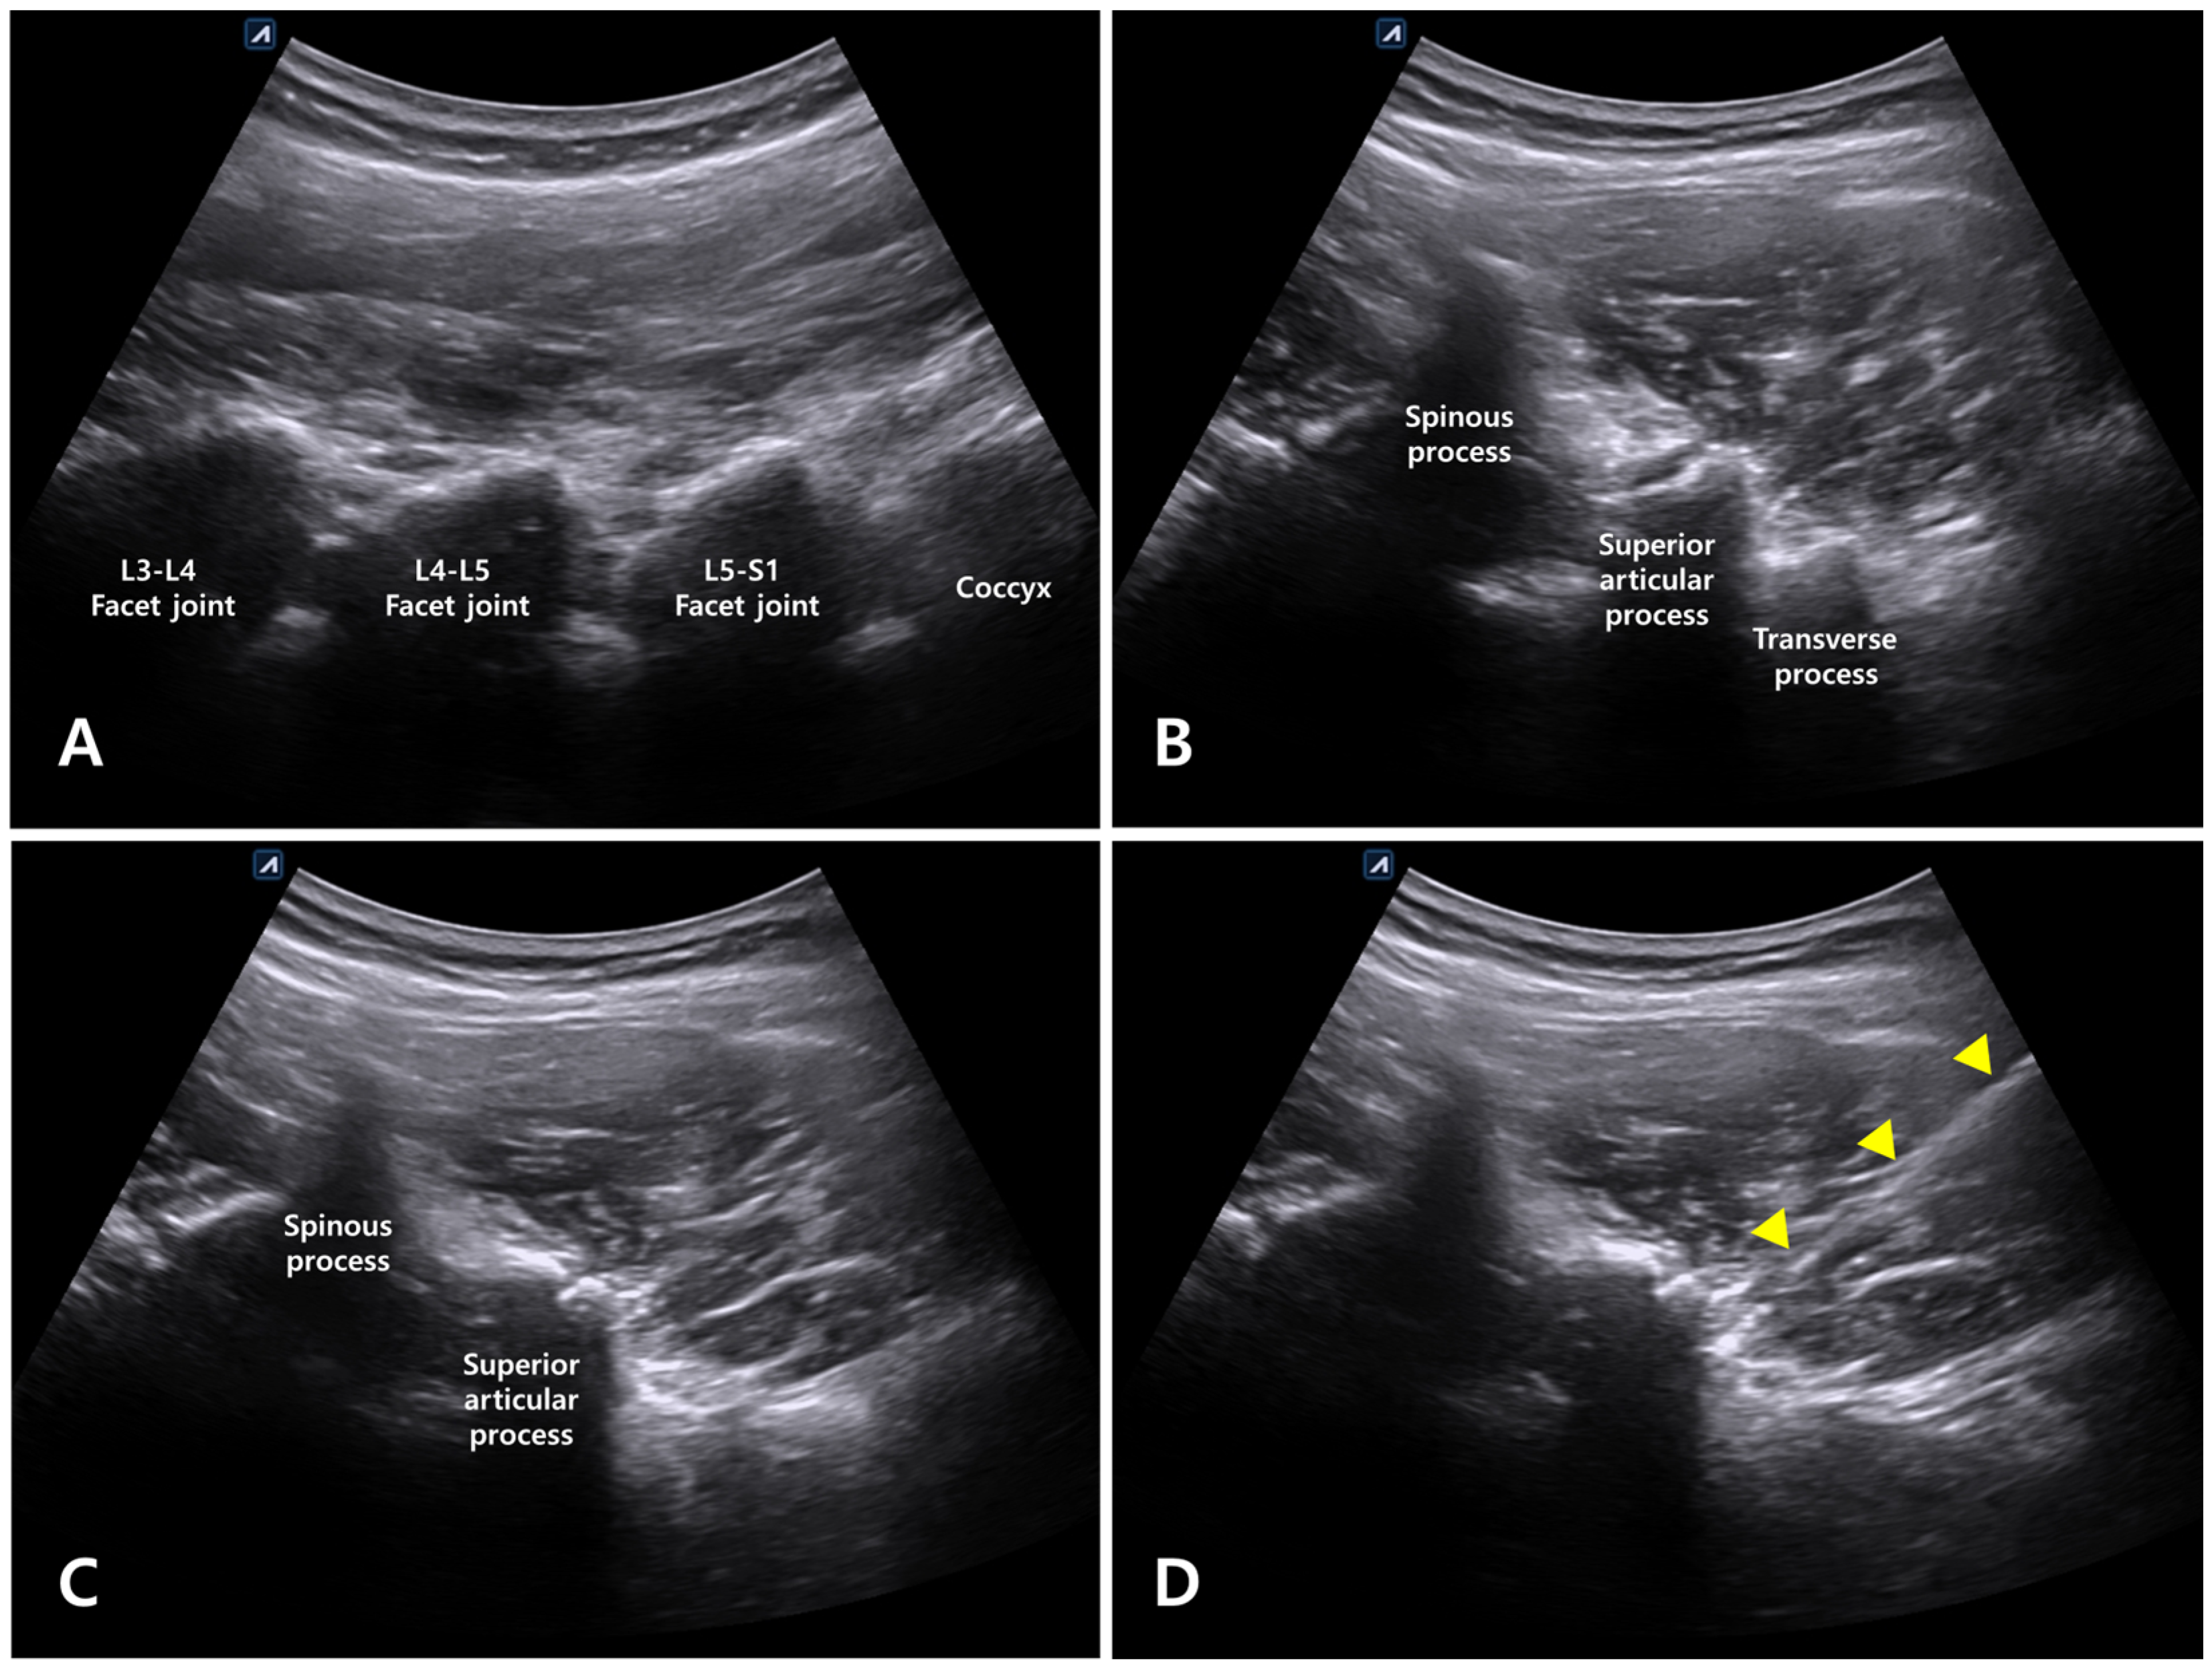

For long-axis scanning of the lumbar spine, the probe was placed on a palpable spinous process at the level of the posterosuperior iliac spine. Subsequently, the probe was moved laterally to identify the appearance of the camel-hump sign, which was determined to be the facet joint (Figure 3A). Next, the probe was moved cranially from the sacrum lying longitudinally, and the vertebral segments L5/S1 and L4/L5 were located and marked according to the order of the joints observed in this direction. From the long-axis view, the target segment for intervention (i.e., the L4–L5 facet joint) was determined, and the probe was rotated by 90° to perform short-axis scanning (Figure 3B). In the short-axis view, with the spinous process placed at the center, the probe was moved so that the superior articular process of the facet joint was displayed at the center of the screen to obtain a paramedian view. The probe was moved caudally from this position to scan the L5 transverse process (Figure 3B,C). Afterwards, the probe was moved cephalad, and the transverse process disappeared; the location for the intervention was determined in this plane (Figure 3D).

Figure 3. Ultrasound-guided Kambin’s triangle approach. (A) In the long-axis view, the facet joint was confirmed via the camel-hump sign. (B) In the short-axis view, the superior articular process of the L4–L5 facet joint, L5 transverse process, and L4 spinous process were observed in one plane. (C) The probe was moved cephalad, the transverse process disappeared, and only the superior articular process and facet joint were observed. (D) In the same plane as Figure (C), the path through which the needle entered Kambin’s triangle (marked with triangles) is shown.